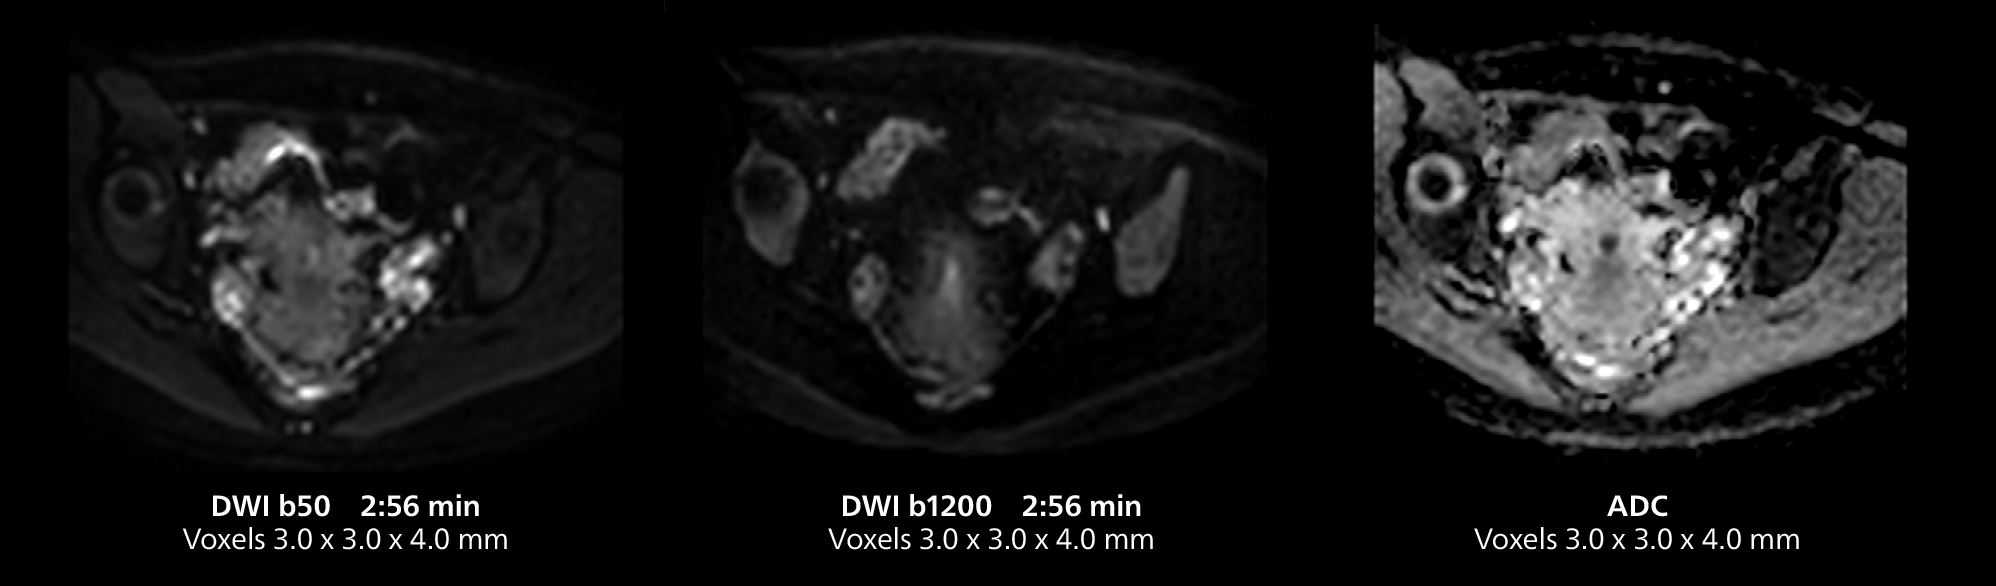

Salivary gland imaging on MR 5300

This MRI case illustrates imaging of salivary gland abnormalities with different sequences. Compressed SENSE allows to accelerate scanning while maintaining high quality. With mDIXON XD, different contrast types can be obtained from scanning one sequence.

Salivary gland imaging on MR 5300

This MRI case illustrates imaging of salivary gland abnormalities with different sequences. Compressed SENSE allows to accelerate scanning while maintaining high quality. With mDIXON XD, different contrast types can be obtained from scanning one sequence.